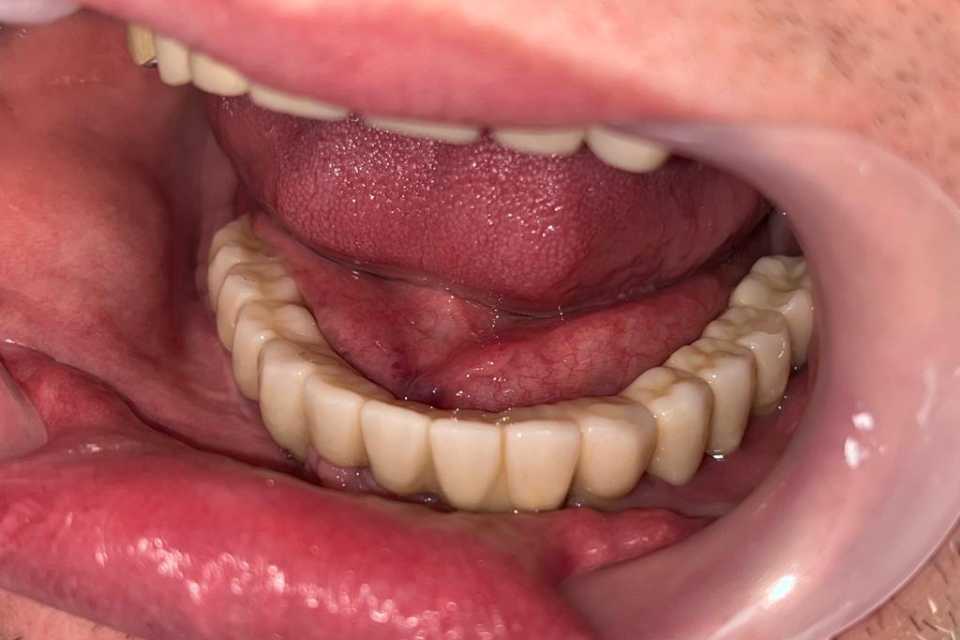

Lucrare fixă înșurubabilă pe implanturi

Cazul 53: All on 6

Pacient în vârstă de 45 de ani, vechi purtator de proteza totală inferioara s a prezentat cu dorința de a efectua o lucrare pe implanturi fixa.

Cazul a fost unul foarte dificil prin prisma resorbtiei osoase în zonele laterale mandibulare și ale patologiilor asociate ale pacientului, prohibitive pentru adiții osoase.

Astfel, am optat, impreuna cu pacientul, pentru 6 implanturi Straumann BLX Roxolid, inserate lateral de nervul alveolar inferior, metodă care ne-a ajutat sa evitam procedura de aditie osoasă, pe care am realizat o lucrare fixa insurubabila din Zirconiu.

Rezultatul final a fost pe masura așteptărilor pacientului.